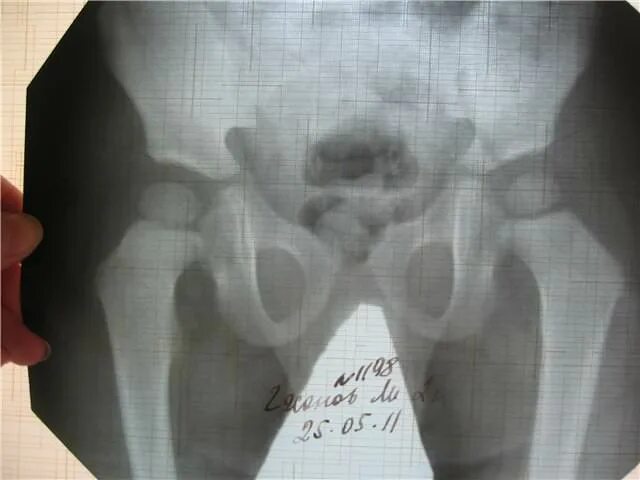

Делала рентген при беременности